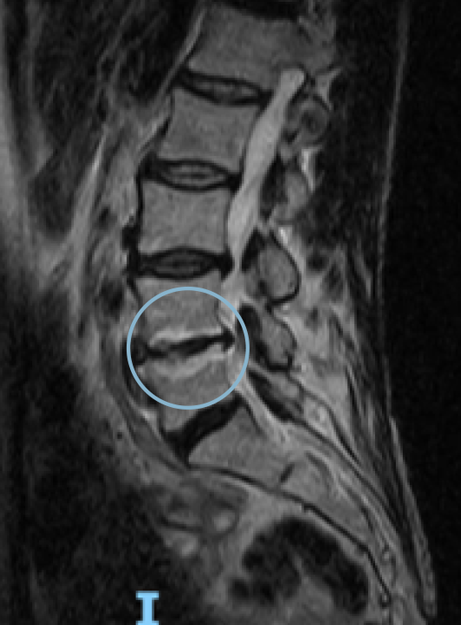

Comparative magnetic resonance imaging of Lumbar spine pre- and one-year post-treatment in a 50-year-old woman diagnosed with lumbar osteoarthritis. The red arrow shows the remodeling of the affected disc

BEFORE